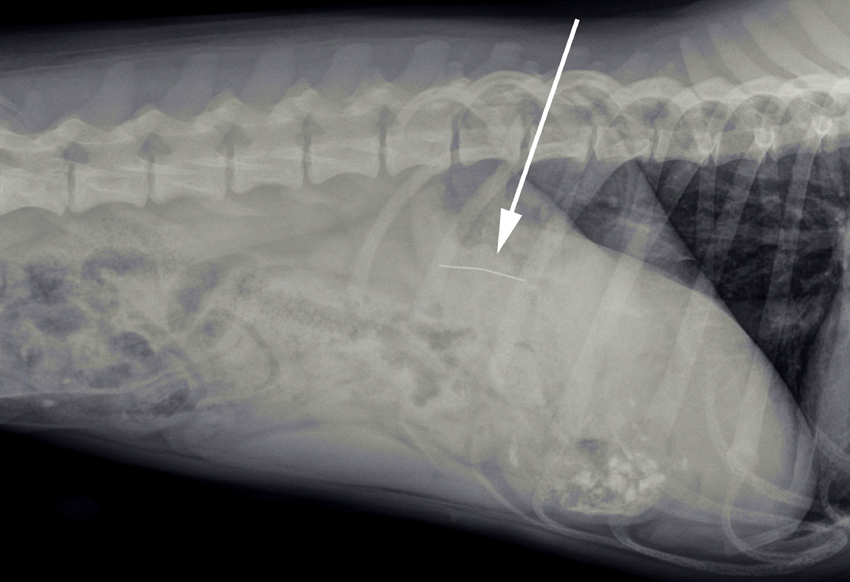

Op de röntgenfoto was de speld duidelijk zichtbaar in de maagstreek. Gelukkig was hij niet in de slokdarm blijven steken.